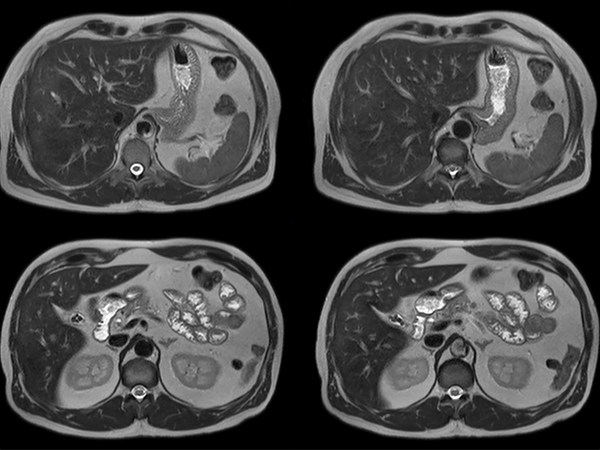

Total Torso imaging - MultiVane XD